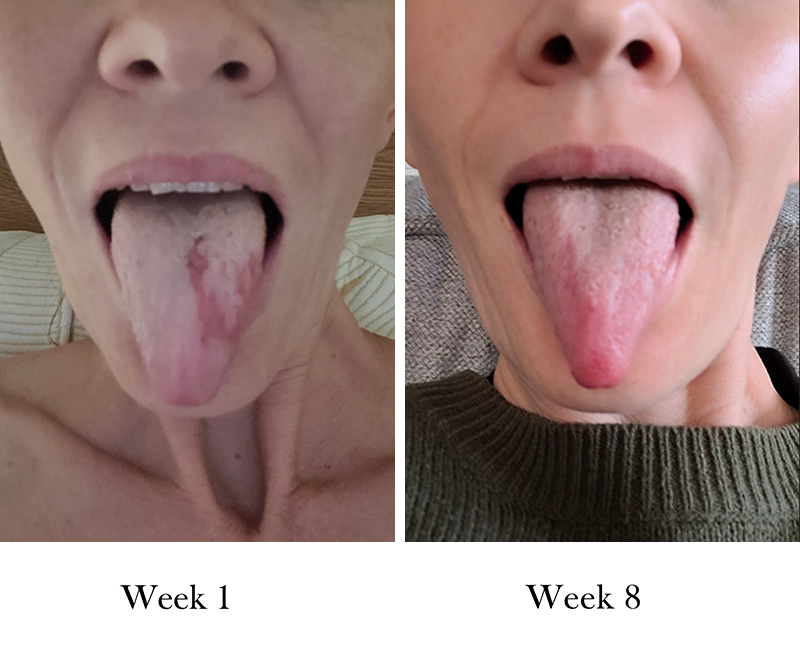

"My geographic tongue condition has almost completely healed, this is absolutely amazing as I have had this issue for around 10 months with zero improvement until now."

Lana

Brilliance Unflavoured